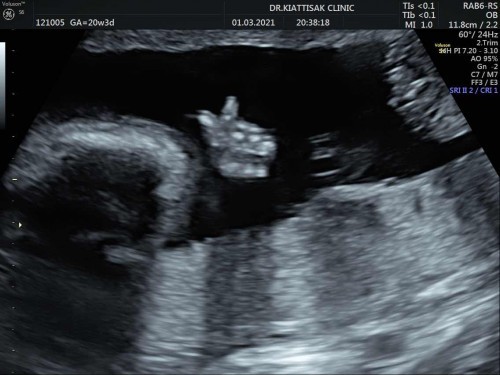

คุณหมอขอดูนิ้วหน่อย ไงเป็นงี้หละลูก 😂

คุณหมอขอนับมือหน่อย ผมทำมินิฮาร์ทโชว์เลยครับแม่ๆ 😂😂😂🎉🎉💝#ท้องแรกคะ

น่ารัก...น้องกี่วีคแล้วคะ

20w4d วันนี้ค่ะแม่